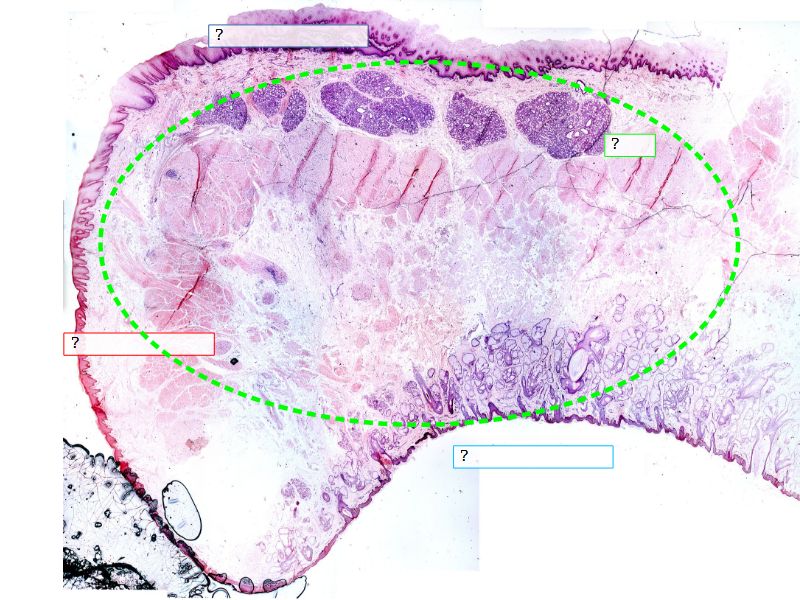

Fill in all the missing labels, and assess as you move through the slides. Answers on the down slide. It is important to do this using pen and paper, and not just glance through the images.